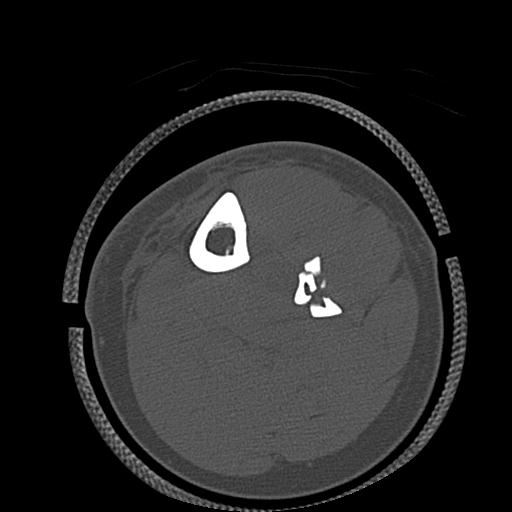

102803 1/12(キウスなし) 1/27 左下腿 4R 30歳女性 左脛骨軸内釘